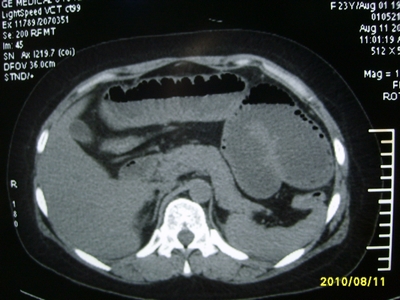

5天前突发腹痛剧烈难忍,伴解淡血水样便。近一天来腹痛缓解,没有明显的腹膜炎的体征。今天照的腹部ct。从ct上看感觉是一个绞窄性肠梗阻,但是现在没有腹痛。不好解释

要有麻烦了,感觉小肠有套叠还有扭转改变,估计部分已有坏死。

高位肠梗阻(不全性),原因小肠(空肠)扭转,肠壁水肿增厚,成年人肠梗阻要排除合并占位,建议手术。

绞窄性肠梗阻_肠管套叠 扭转,肠壁明显水肿。

支持绞窄性肠梗阻,肠壁明显水肿并见有多发小泡状积气--肠坏死

考虑绞窄性肠梗阻并肠坏死。